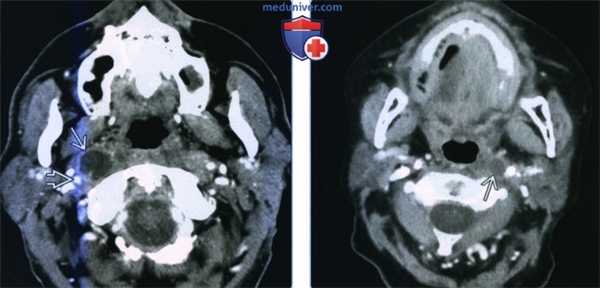

(Слева) КТ с КУ, аксиальный срез на уровне носоглотки. В латеральном отделе заглоточного пространства, медиальнее правой внутренней сонной артерии визуализируется крупный некротизированный лимфоузел. У взрослых при подозрении на злокачественное поражение лимфатических узлов наиболее вероятной причиной является плоскоклеточный рак глотки.

(Справа) КТ с КУ, аксиальная проекция, пациент с плоскоклеточным раком ротоглотки. Метастатическое поражение левого заглоточного лимфоузла, которое привело к его кистозному перерождению. При проведении ПЭТ захвата ФДГ не наблюдалось. Кистозные лимфоузлы могут стать причиной ложноположительных результатов при проведении ПЭТ.

2. КТ при метастазах плоскоклеточного рака в заглоточные лимфоузлы:

• КТ с КУ:

о При КТ лимфоузлы визуализировать сложно, особенно небольшие

о Образование округлой или овальной формы, мягкотканной плотности и умеренно накапливающее контрастное вещество

о Некроз лимфоузла: центральный участок пониженной плотности, который окружен различной толщины стенкой, накапливающей контрастное вещество

о Нечеткие контуры ± исчерченность окружающей жировой клетчатки: экстракапсулярное распространение опухоли